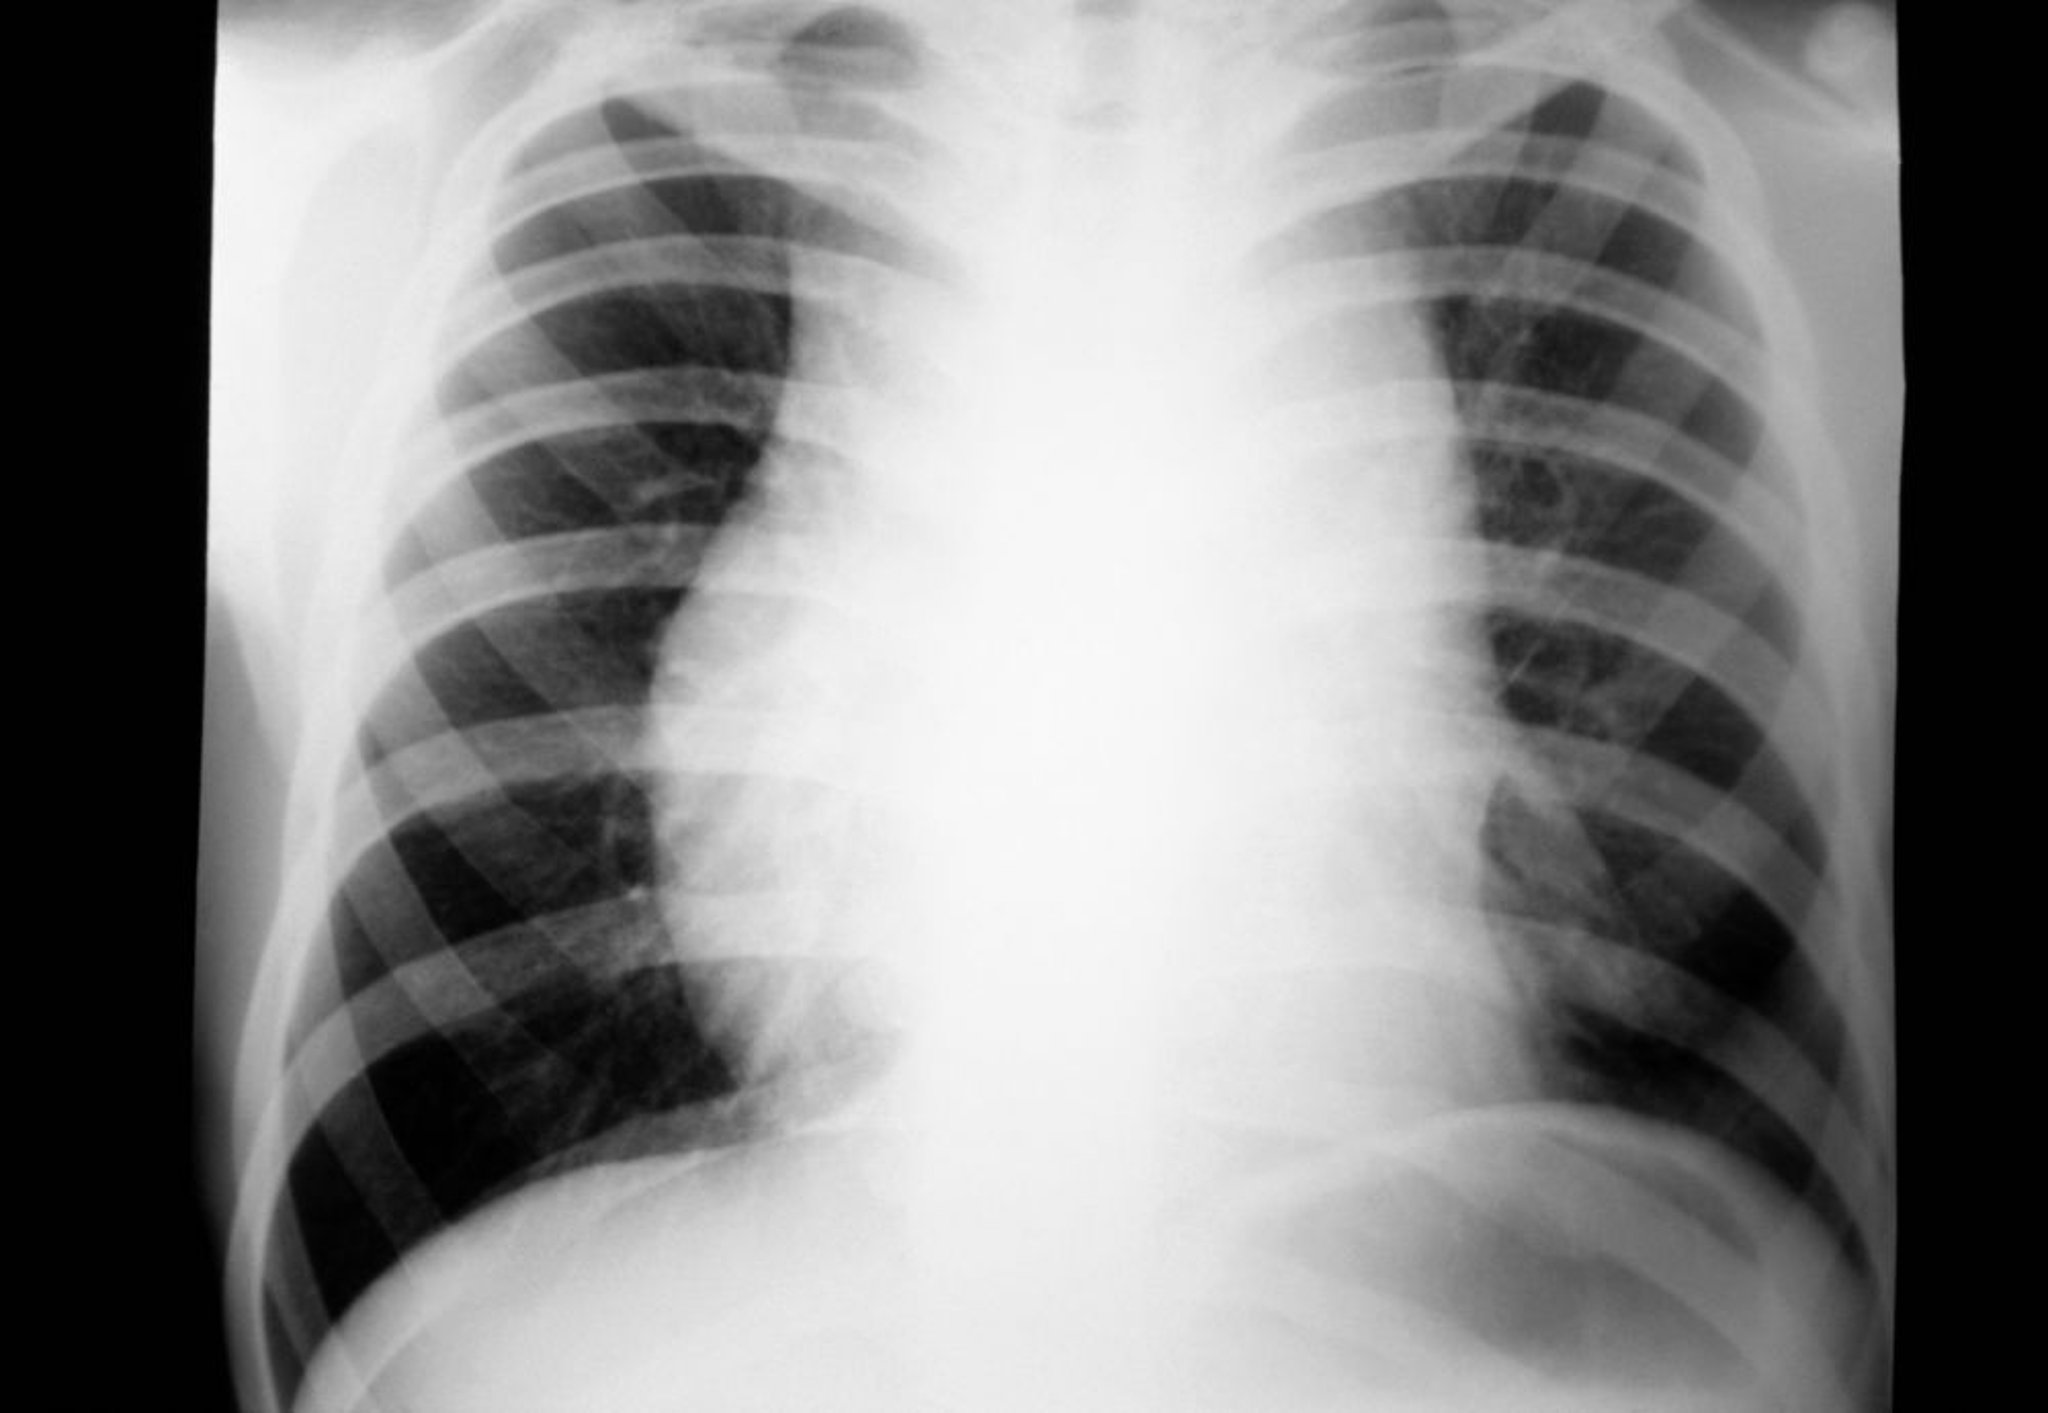

Linfoma de Hodgkin (adenopatías mediastínicas)

Radiografía de tórax de un paciente con linfoma de Hodgkin que muestra adenopatías mediastínicas.